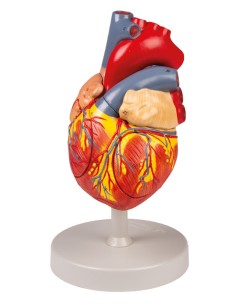

Des modèles anatomiques détaillés pour tous les besoins

Du crâne en 22 parties à verrouillage magnétique aux modèles de colonne vertébrale, des modèles d'articulation aux modèles de cœur, chaque pièce de notre collection est conçue pour une immersion totale dans l'étude de l'anatomie humaine. Nos modèles, réalisés à partir de scans d'os réels, garantissent une expérience tactile authentique et une fidélité de poids presque identique aux originaux.

Indispensables aux étudiants comme aux professionnels, nos modèles anatomiques sont des outils pédagogiques qui permettent d'observer les structures anatomiques avec précision, en évitant les dissections ou les études invasives. Ils sont également utiles pour expliquer les pathologies aux patients, ce qui rend la communication plus efficace et permet de gagner un temps précieux.